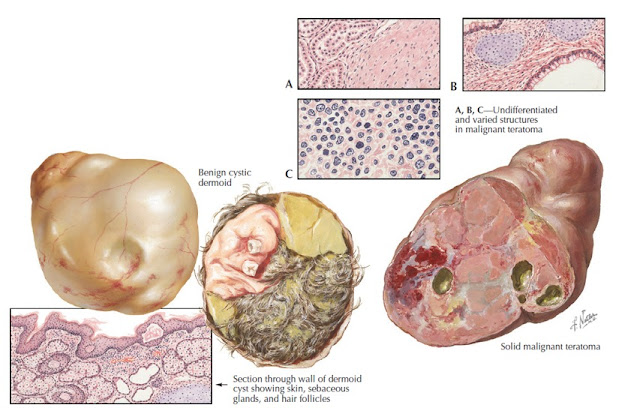

Las características macroscópicas del tumor dependen de la tasa de crecimiento, los tumores de crecimiento lento son bien circunscritos, redondos o multilobulares, rodeados de una pseudocápsula lisa. Los tumores poco diferenciados y tumores de rápido crecimiento son poco circunscritos con una apariencia heterogénea, a menudo con áreas necróticas y hemorragia.

Los dos subtipos principales son; monofásico y bifásico, siendo el primero el más frecuente. Entre los subtipos menos frecuentes comprenden los siguientes; pobremente diferenciado (células redondas), epitelial monofásico, calcificante/osificante y el mixoide.

Desde el punto el punto de vista histopatológico, el sarcoma sinovial presenta múltiples variantes morfológicas, lo que hace difícil su diagnóstico. Puede simular otras neoplasias mesenquimales fusocelulares tales como; el fibrosarcoma, el tumor maligno de la vaina nerviosa periférica, tumor fibroso solitario, etc, que presentan vasos sanguíneos “hemangiopericíticos”. Morfológicamente el principal diagnóstico diferencial en nuestro caso es un tumor maligno de la vaina nerviosa periférica, en este caso no se pudo realizar estudios para biología molecular, siendo ideal H3K27me3 para descartar esta entidad, y biología molecular para SS18. Sin embargo, morfológicamente nuestro caso no presentó zonas de celularidad alternante (hipercelular e hipocelular), tampoco se observó necrosis extensa con áreas perivasculares conservadas, ambos hallazgos se presentan con mucha frecuencia en el tumor maligno de la vaina nerviosa periférica, por lo que favorecemos el diagnóstico de sarcoma sinovial en nuestro caso.